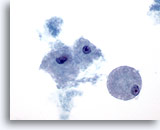

Figure 14

Breast FNA, Fibrocystic changes.

This small group of benign ductal cells is from an aspirate of fibrocystic changes. 40x

Figure 14

Breast FNA, Fibrocystic changes.

This small group of benign ductal cells is from an aspirate of fibrocystic changes.

40x